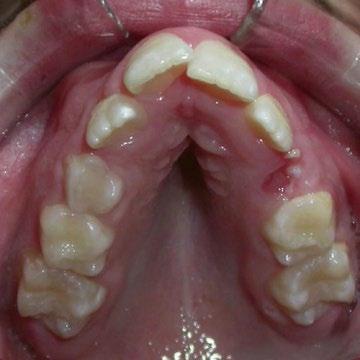

• Cara mas alargada; con la lengua baja el tercio medio inferior recibemenos estimulación, descompensando el maxilar y la mandíbula ydando lugar a mordidas abiertas, sobremordida, apiñamiento...

Alteración en el habla por un paladar estrecho retrasando la pronunciación y dificultando el avance en logopedia ya que la lengua no encuentra espacio, pudiendo esto frustrar al niño.

Deglución atípica: la lengua empuja los dientes alterando la masticación y produje ruidos al tragar.